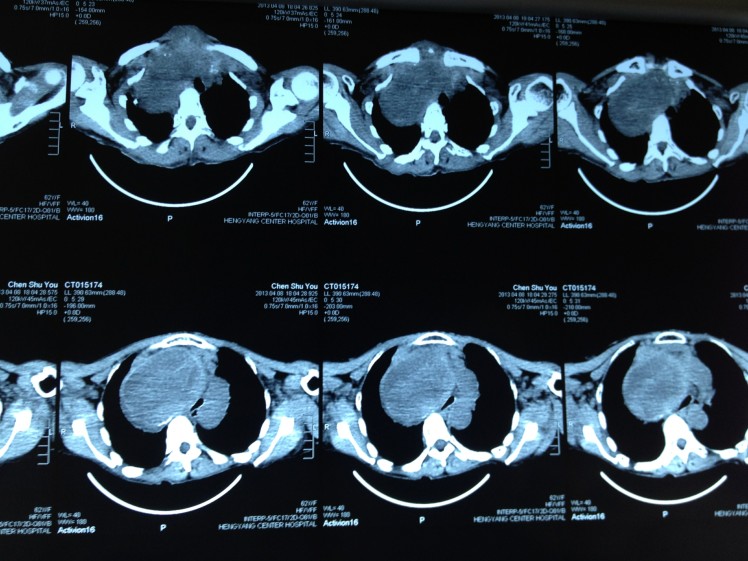

因氣管被甲狀腺巨大腫塊壓迫成“一線天”而險些窒息的陳阿婆,經(jīng)過我院乳甲外科尹軍主任主刀手術(shù),已經(jīng)康復(fù)出院。如今,困擾她十多年的胸悶、氣促也已從根本上得到了解決。

4月8日,62歲的陳阿婆因呼吸困難在家中險些窒息而被家人背送我院乳甲外科就診。陳阿婆發(fā)現(xiàn)頸部雙側(cè)腫塊已有30余年,曾就診于省內(nèi)多家大型醫(yī)院,大多專家建議開胸手術(shù),手術(shù)費(fèi)高達(dá)10余萬元,有些醫(yī)院甚至考慮手術(shù)難度大、風(fēng)險高就干脆拒收入院。我院乳甲外科尹軍主任將患者收住院后,會同醫(yī)務(wù)部組織了麻醉科、放射科、胸外科、呼吸內(nèi)科、心內(nèi)科的專家會診,進(jìn)行術(shù)前討論,制定了周密的手術(shù)方案。